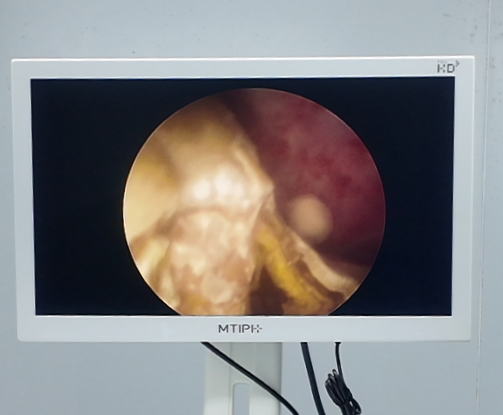

手术中,王华勋主任利用国际领先的铥激光碎石系统,把任先生的多发性结石逐一高效粉末化,同时结合智能负压清石系统,实现“边碎边吸,即时清空”,在精准清除结石的同时,最大程度保护了肾脏功能。